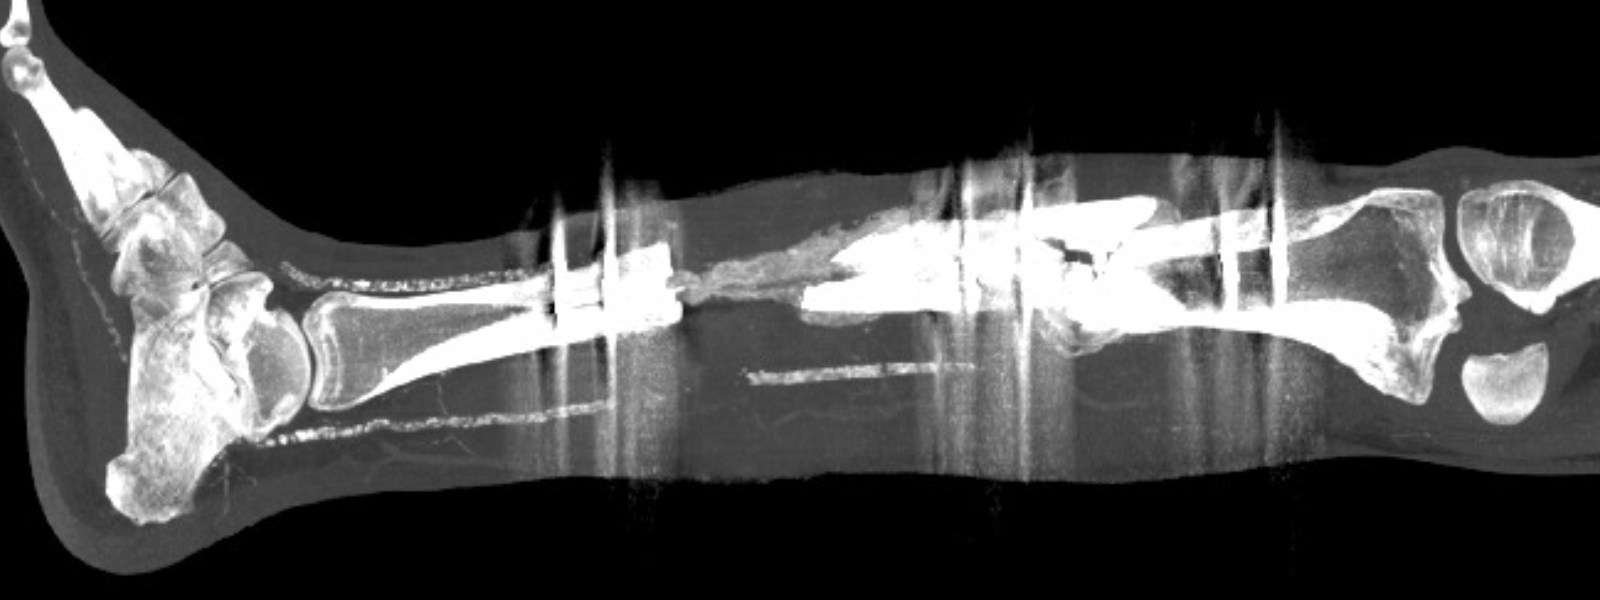

Bone defects

These are areas of bone that have been damaged or lost due to trauma, infection, surgery, or disease, which may compromise the stability, function, and/or integrity of the affected bone. These defects vary in size and severity and can be partial (affecting only a portion of the bone) or segmental (involving the loss of an entire bone segment). Accurate diagnosis is essential to plan reconstruction, prevent deformities, and restore the function of the affected limb.

Treatment depends on the size, location, underlying cause, and the patient’s overall condition.